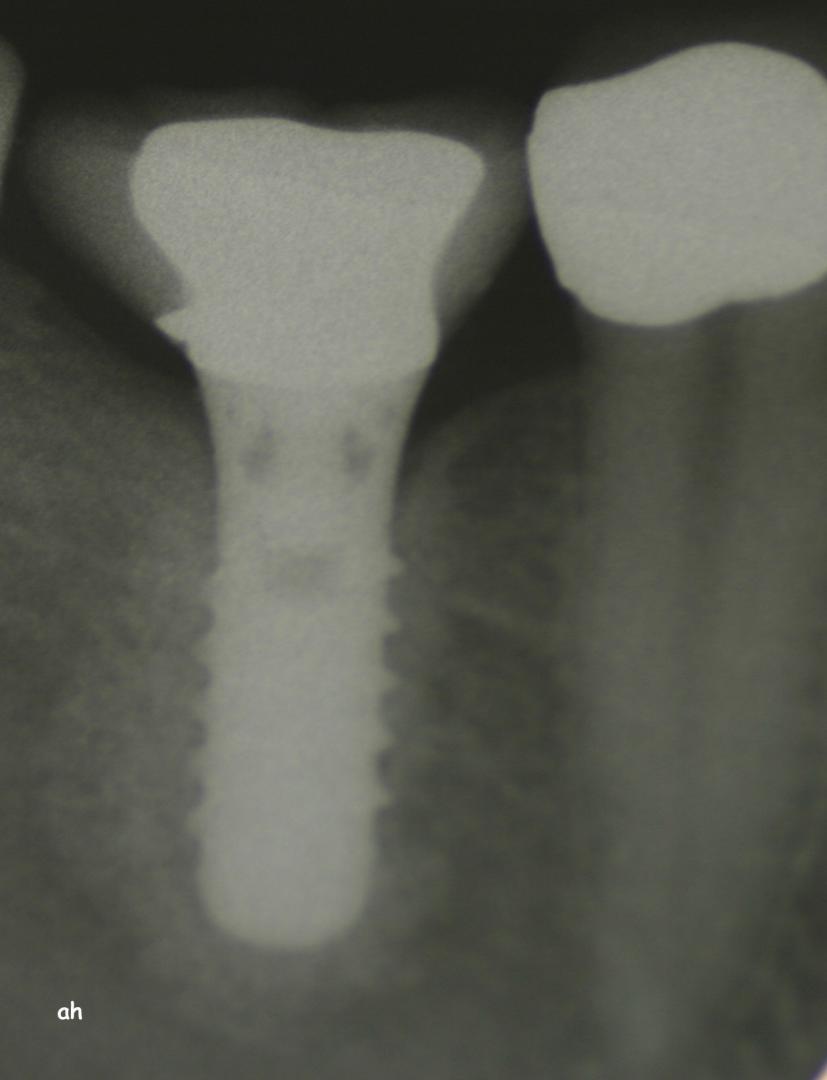

Exemple 14: Radiographie post chirurgicale.

Exemple 14: 6 mois plus tard, l'implant est introduit dans cette greffe sans toucher le sinus.